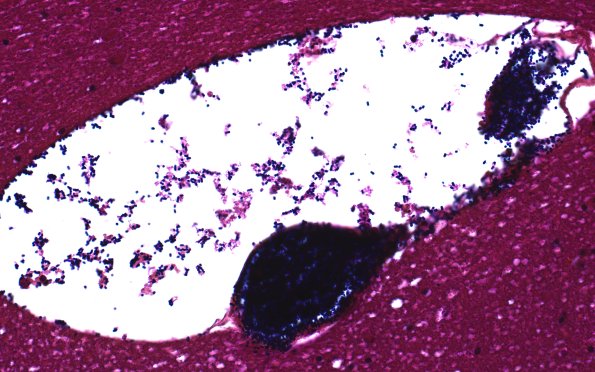

Washington University Experience | BASIC PROCESSES | Artifacts | Artifact - Swiss Cheese Brain | 34C1A Swiss Cheese Brain (Case 12) Gram Best 40X

34C1A,B This Gram stain shows Gram positive cocci, which outnumber bacillary forms. (Gram)